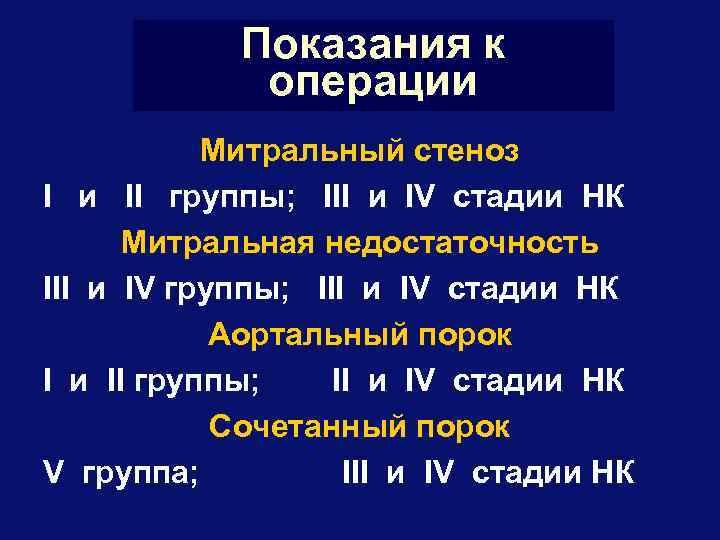

Показания к операции Митральный стеноз I и II группы; III и IV стадии НК Митральная недостаточность III и IV группы; III и IV стадии НК Аортальный порок I и II группы; II и IV стадии НК Сочетанный порок V группа; III и IV стадии НК